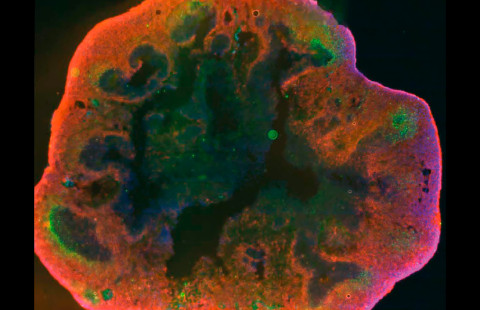

Nuorempi tutkija Ilkka Fagerlund tekee työkseen sellaista, mitä ei moni tee. Hän valmistaa laboratoriossa aivo-organoideja – eräänlaisia miniaivoja, joita voidaan käyttää aivosairauksien tutkimiseen.